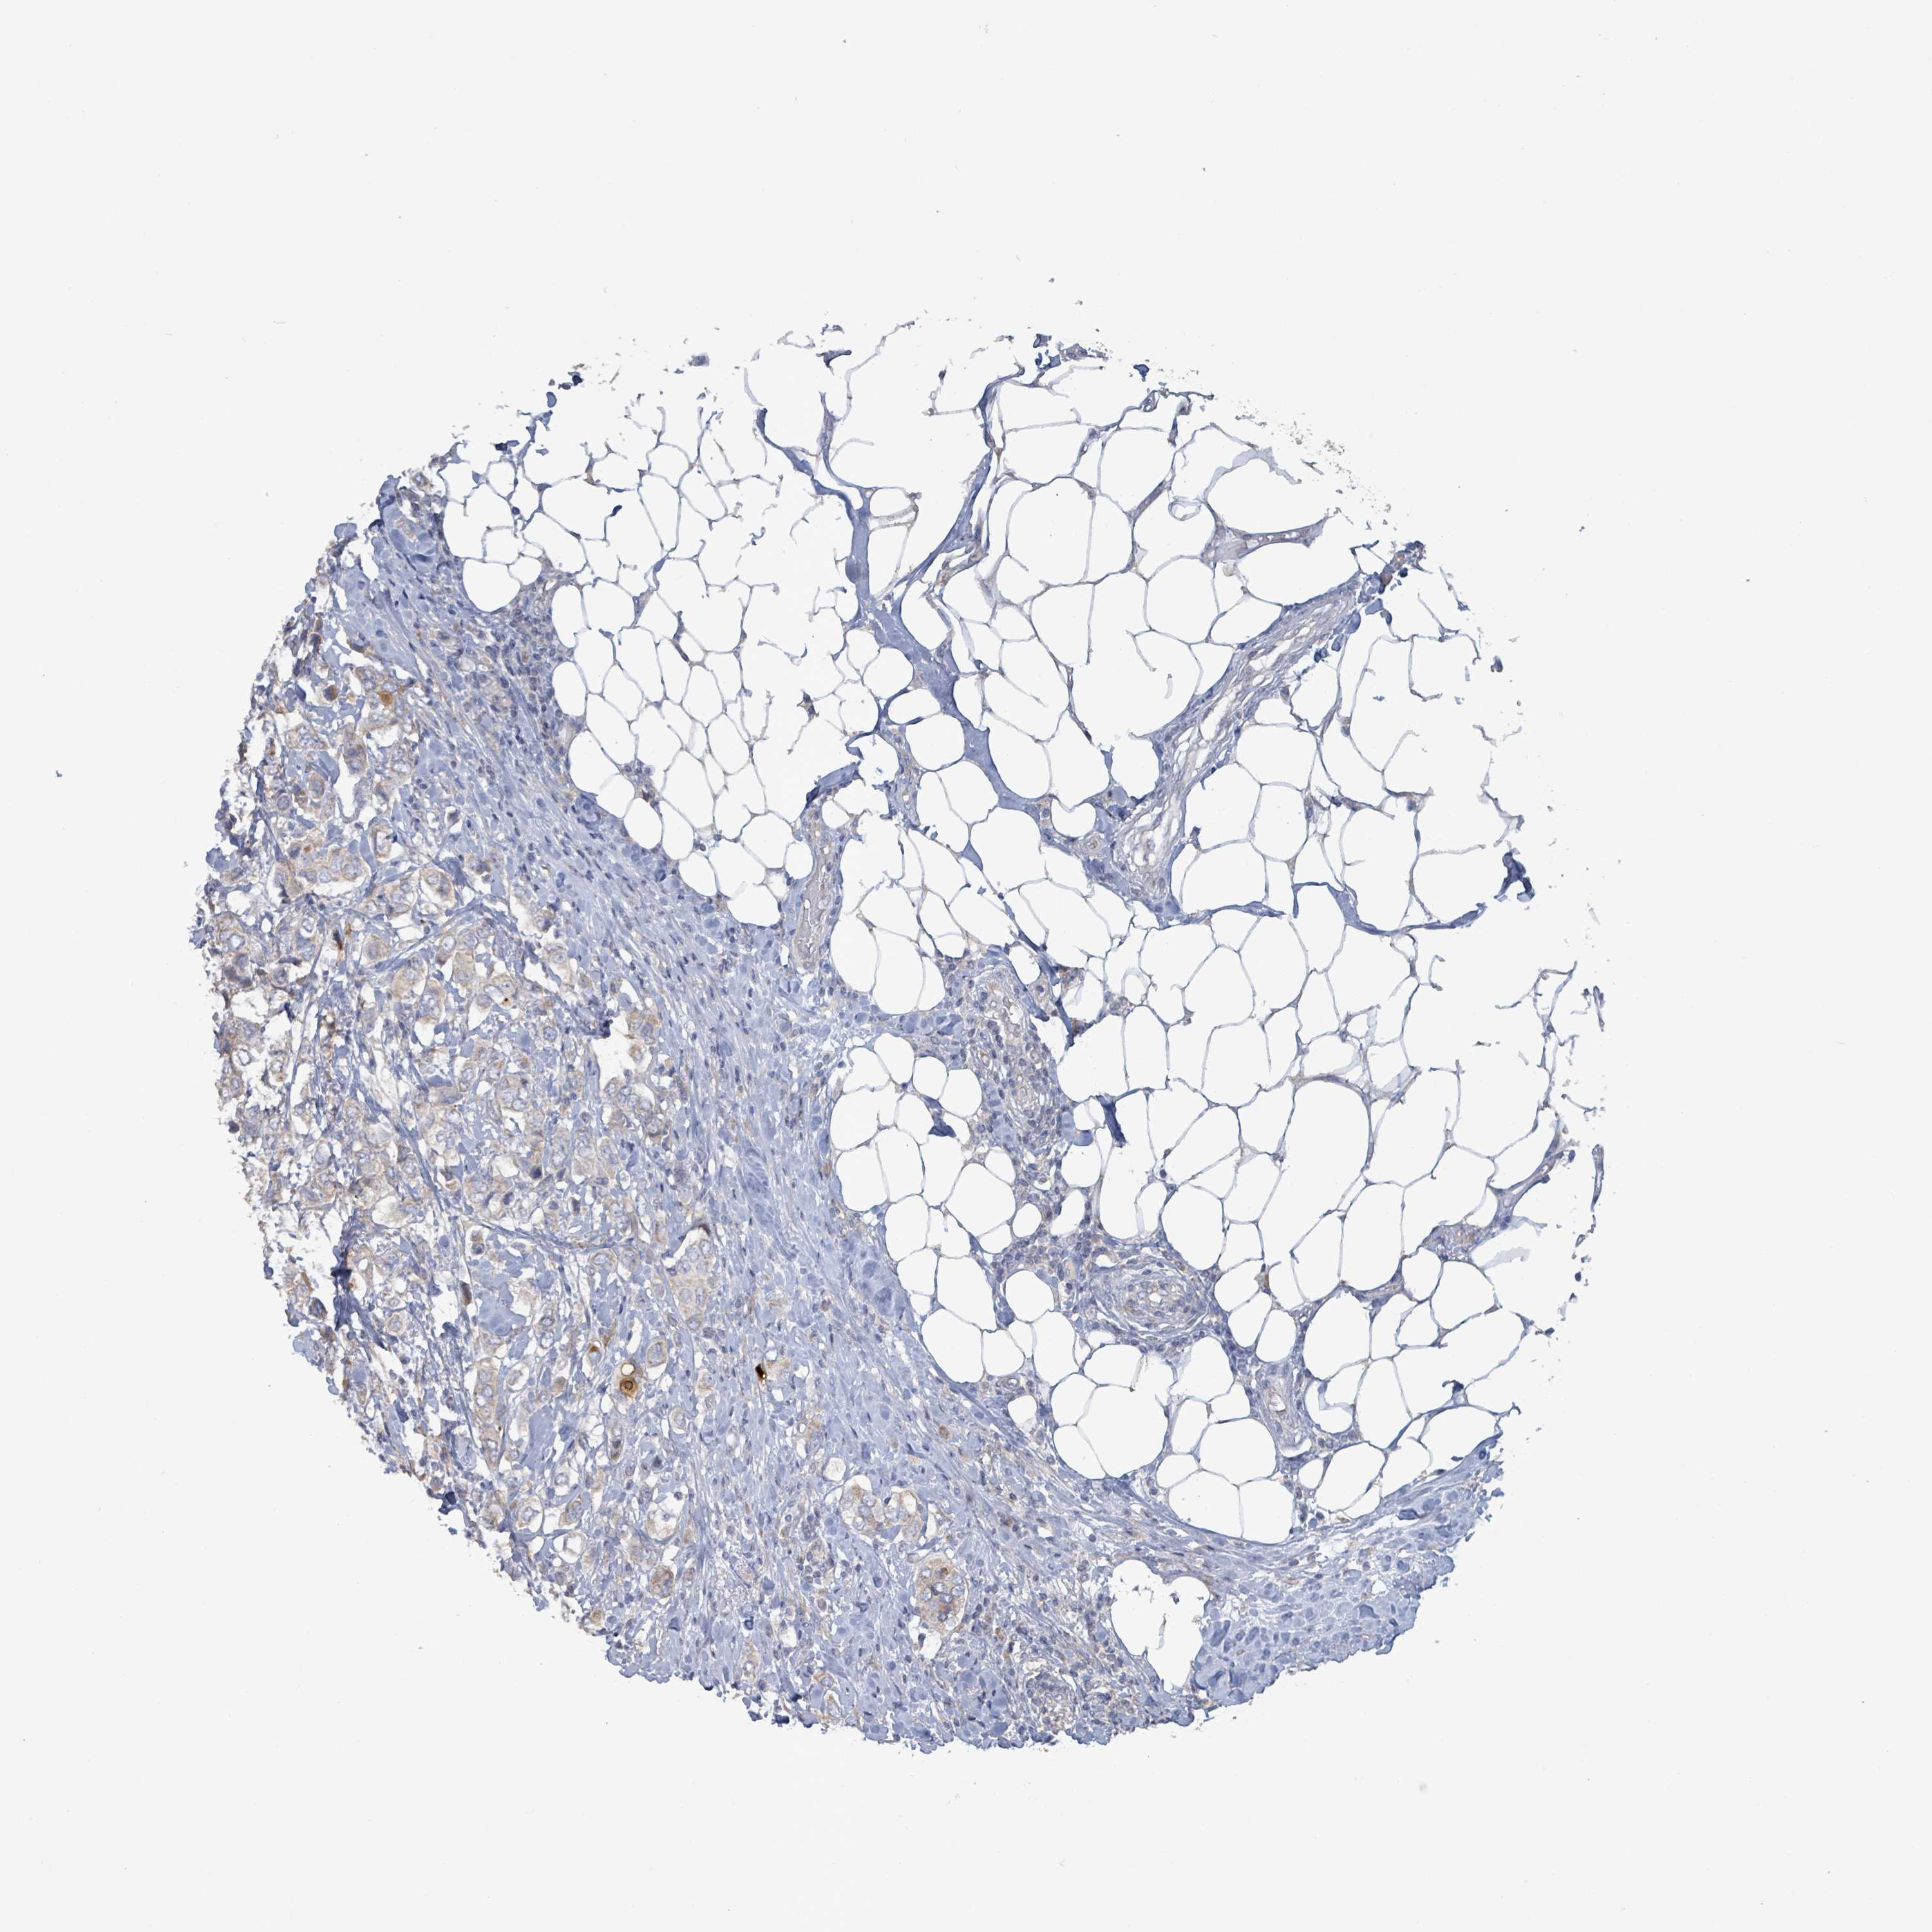

BRCA TCGA BRCA VALIDATION PROTEIN EXPRESSION